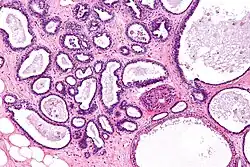

![]() | Mucinous cystadenoma | Micrograph showing Mucinous Cystadenoma of ovary. The cyst wall is lined by tall columnar epithelium and filled with mucin. | Category: Histopathology of mucinous cystadenoma | Mucinous cystadenoma |